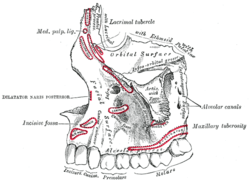

Position of nasalis muscle (shown in red).

Position of nasalis muscle (shown in red). Left maxilla. Outer surface.

Left maxilla. Outer surface.